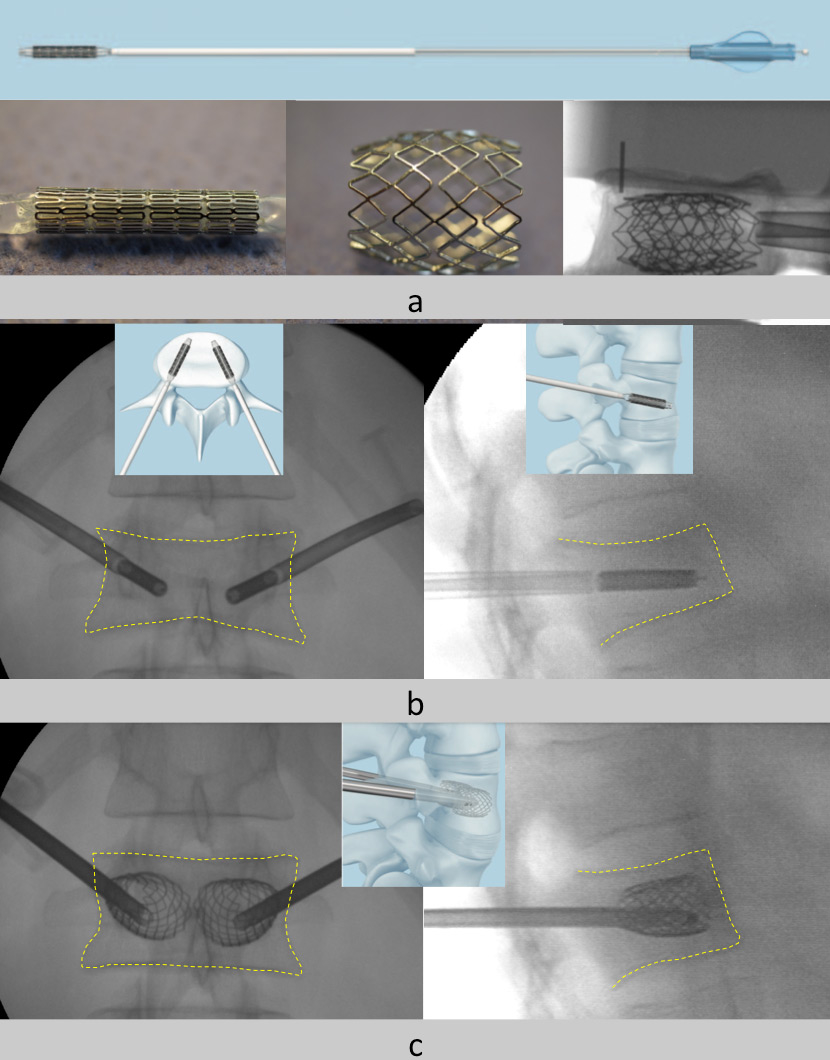

Figure 2

The vertebral body stent principle: A 4 mm stent with different lengths can be expanded up to 400%. It can provide preliminary stability and maintain the height gain before cement is injected; it cannot work as a standalone device (a). The stents are placed on each side through the pedicles (b). The stent is then expanded by the balloon. In this way the vertebral height (c) is restored. The final stabilisation is performed by the injection of bone cement (not shown here). The contours of the vertebral body are outlined by the yellow dashed lines.

Normally VBCF are treated conservatively. However, in patients with severe pain stabilisation of the vertebral body with bone cementis now well accepted [4, 5]. The procedure consists in the injection of highly viscous cement directly into the fractured vertebral body (vertebroplasty) or by prior cavity creation with a balloon (kyphoplasty). These procedures do not allow real restoration of the compressed vertebral body, and further extension of the technique consists in vertebral body stenting, also called stentoplasty [6]. The principle resenbles that for vascular stents – a balloon mounted stent is expanded and in this way the vertebral body is lifted and, as a preliminary move, stabilised by the stent. For final stabilisation bone cement is injected. The stent can be expanded by some 400%, from 4.2 mm to 17 mm. (fig. 2). Based on in vitro experiments, greater height gain with the stent was demonstrated when compared to the balloon-only technique (fig. 3). For all patients with an osteoporotic fracture, assessment of bone metabolism and adequate medical treatment of osteoporosis are mandatory [7, 8].

Stentoplasty represents a percutaneous minimally invasive intervention resembling a vertebroplasty or kyphoplasty procedure. Two balloon mounted stents are placed through the pedicles of the fractured vertebral body. The balloons are then deployed by a inflation system under fluoroscopic guidance until the vertebral height is restored. The balloons are then retrieved and the stent and the surrounding bone is filled with bone cement. The intervention is performed in prone position, under either local/stand-by or general anaesthesia. The duration of the procedure is some 45 minutes. The patient is allowed to get up as soon as this is tolerated and is free to resume activity depending on pain. Usually the intervention is performed within a short hospital stay of two days.

In our series the best potential for height gain was observed in fresh traumatic fractures (n = 6). The healthy bone provides an optimal counterfort for application of reduction forces by the stent (fig. 2).